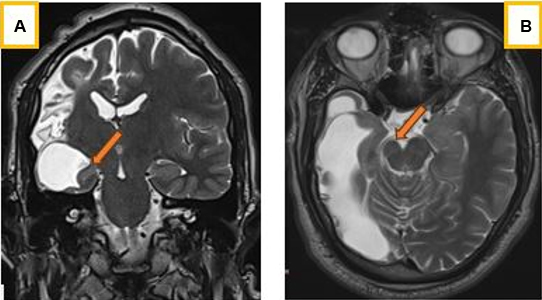

Radiologically, the cerebral hemispheres were asymmetrical, with reduced volume of the right hemisphere (Figure 1 and Figure 2), which was the site of a leukomalacia lesion with compensatory enlargement of the homolateral lateral ventricle (Figure 2). There was also widening of the homolateral cortical sulci, which was more marked opposite the leukomalacia focus, hyperpneumatization of the frontal sinuses (Figure 1) and calvarial thickening, predominantly on the lesion side (Figure 3A), but also of the mastoid cells, which had a compensatory appearance (Figure 3B). It was associated with discrete atrophy of the right cerebral peduncle (Figure 4A) and a reduction in homolateral hippocampal volume (Figure 4B).

Computed tomography (CT) imaging, especially magnetic resonance imaging (MRI), is theore essential for accurate diagnosis, assessment of severity and appropriate management [9],[10]. It classically describes cerebral hemiatrophy, usually accompanied by ipsilateral compensatory bone hypertrophy, such as thickening of the ipsilateral calvaria, hyperpneumatization of the frontal sinuses and mastoid cells, and elevation of the orbital roof and petrous ridge and contralateral hemiparesis [7],[11]. This asymmetry in the prominent development of the frontal sinus may be accompanied by an increase in the thickness of the diploe of the frontal bone on this side. It may be associated with mesencephalic and/or hippocampal atrophy [8], as was the case in our patient.